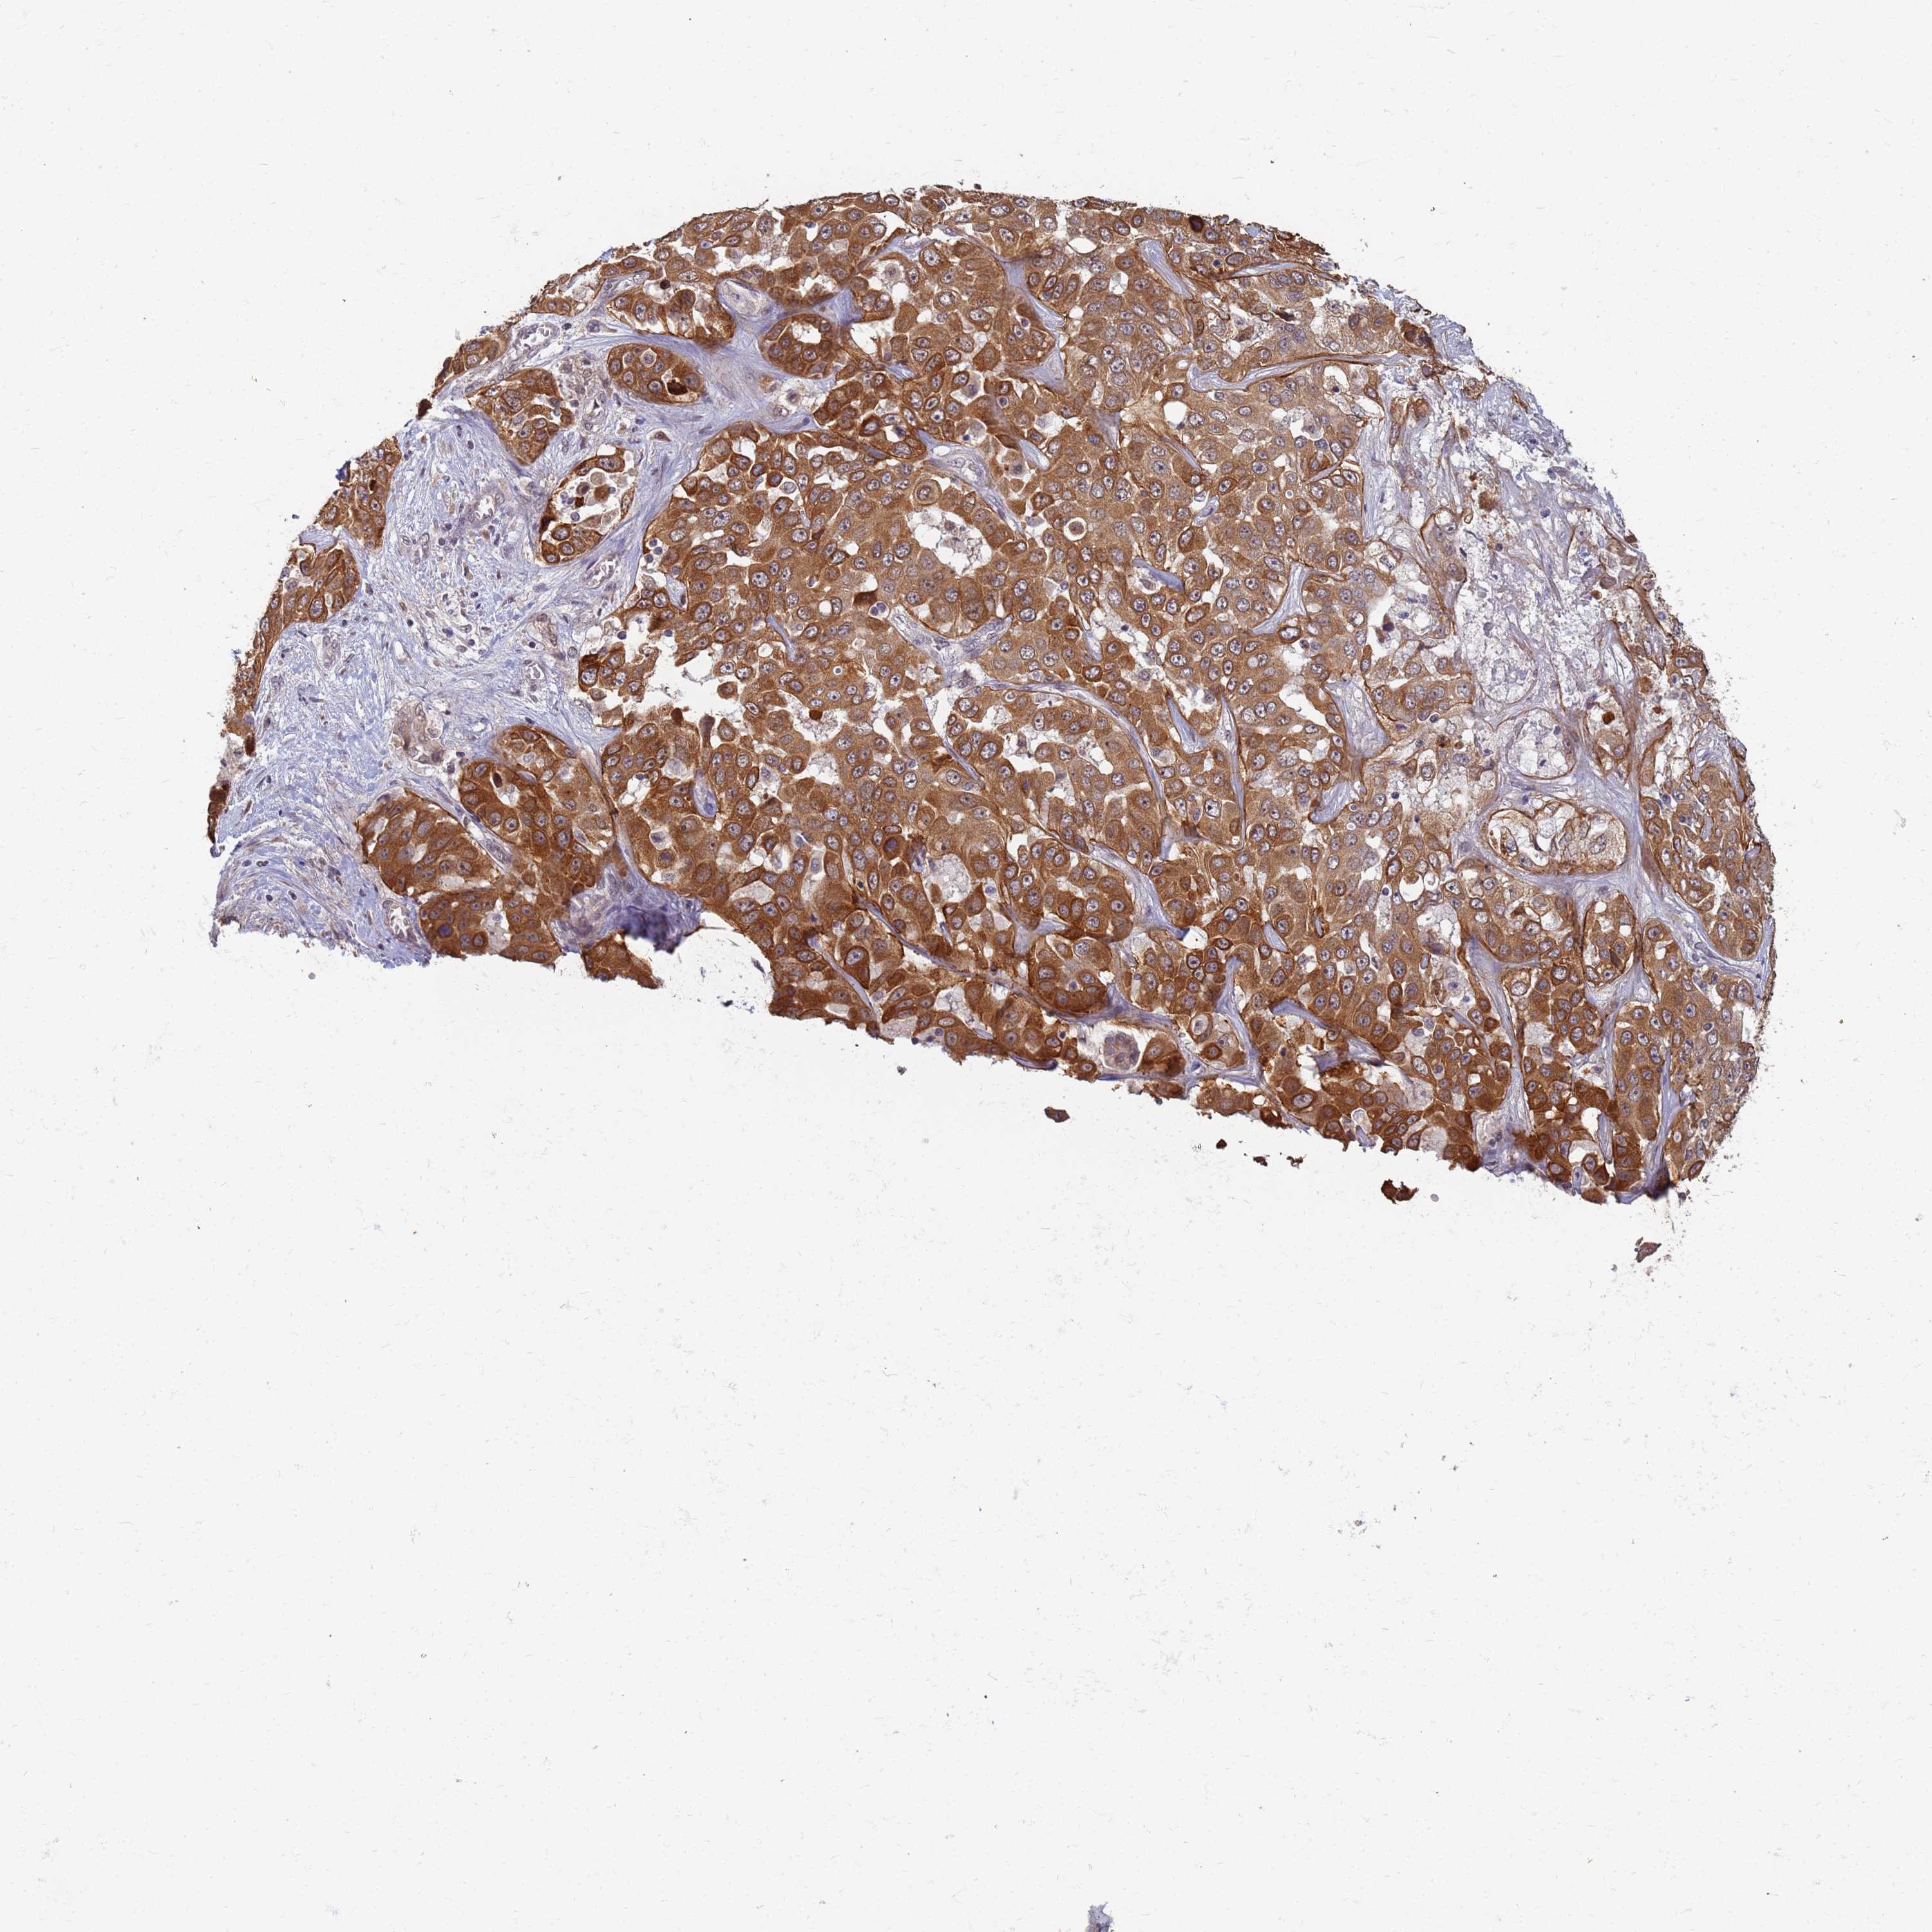

LIVER CANCER - Protein expressioni

A mouse-over function shows sample information and annotation data. Click on an image to view it in a full screen mode. Samples can be filtered based on level of antibody staining by selecting one or several of the following categories: high, medium, low and not detected. The assay and annotation is described here.

Note that samples used for immunohistochemistry by the Human Protein Atlas do not correspond to samples in the TCGA dataset.

Antibody stainingi

Antibody staining in the annotated cell types in the current human tissue is reported as not detected, low, medium, or high, based on conventional immunohistochemistry profiling in selected tissues. This score is based on the combination of the staining intensity and fraction of stained cells.

Each image is clickable and will lead to virtual microscopy that enables deeper exploration of all samples and also displays staining intensity scores, fraction scores and subcellular localization as well as patient and tissue information for each sample.

Antibody HPA036348

Antibody HPA036349

Antibody CAB002422

Antibody CAB005258

Cholangiocarcinoma

Carcinoma, Hepatocellular, NOS